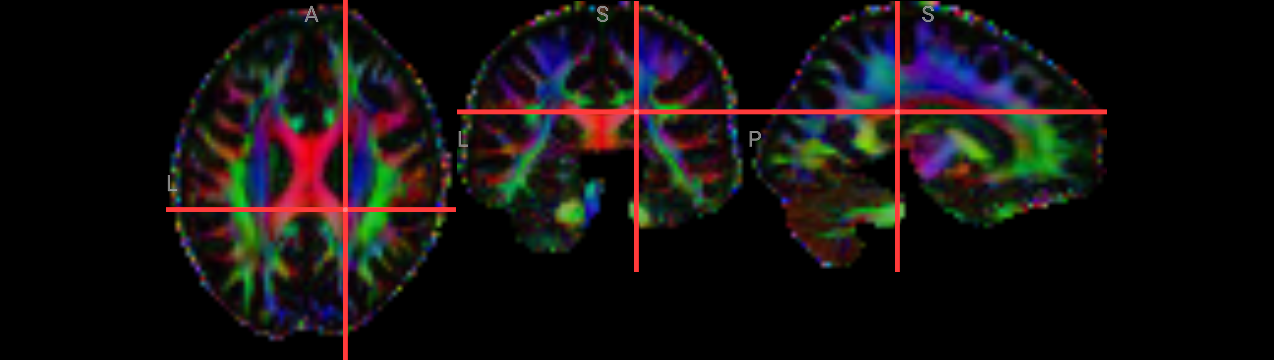

stderr 2025-11-10T00:50:59.619948:*+ WARNING: If you are performing spatial transformations on an oblique dset,

251110-00:50:59,620 nipype.interface INFO:

stderr 2025-11-10T00:50:59.619948: such as ds001226/sub-CON02/ses-preop/anat/sub-CON02_ses-preop_T1w.nii.gz,

251110-00:50:59,621 nipype.interface INFO: